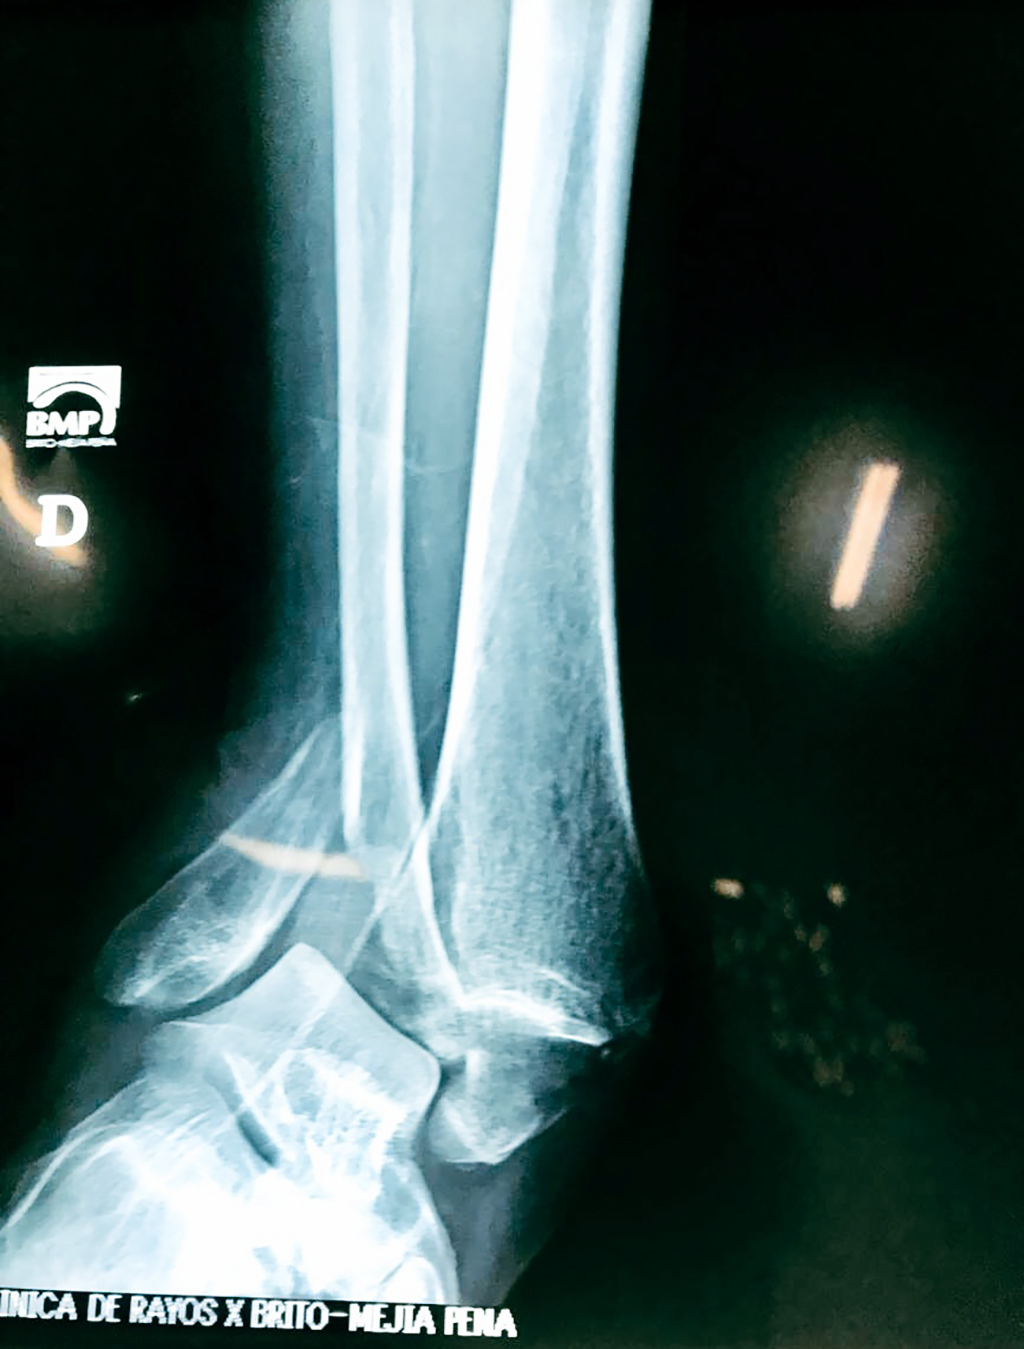

Una fractura de tobillo es la rotura de uno o más de los huesos del tobillo. Estas fracturas pueden ser:

- Parciales (el hueso está sólo parcialmente fisurado, no del todo).

- Completas (el hueso está perforado y está en 2 partes).

- Los tendones o ligamentos (tejidos que sujetan los músculos y los huesos entre sí) están rotos.